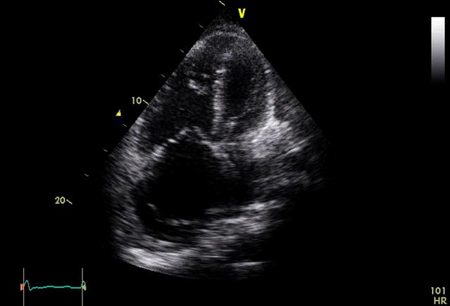

Pulmonary artery systolic pressure (sPAP) is considered equal to right ventricular systolic pressure (RVSP) in the absence of pulmonic valve stenosis and outflow tract obstruction. RVSP is estimated on the basis of Doppler-acquired tricuspid regurgitation (TR) jet velocity plus estimated right atrial pressure from inferior vena cava (IVC) assessment. IVC-based estimation of right atrial pressure is prone to inaccuracy and can lead to amplification of measurement errors when calculating sPAP.[42] Correlation with right heart catheterisation measurements is variable (r from 0.57 to 0.93), and is more robust for sPAP >50 mmHg and <100 mmHg.[39] Sensitivity and specificity of the estimated sPAP in predicting pulmonary arterial hypertension ranges from 79% to 100%, and 60% to 98%.[43] TR velocity (TRV) should be used for screening for PH; a peak TRV of >2.8 m/s is suggestive of PH. TRV should be used with other transthoracic echocardiographic measures of RV function including the tricuspid annular plane systolic excursion (TAPSE), RV fractional area change (RV-FAC), RV free-wall strain, and tricuspid annulus velocity (S′ wave) derived from tissue Doppler imaging, and potentially RV ejection fraction (RVEF) derived from 3D echocardiography.[3] The TAPSE/sPAP ratio measures RV arterial coupling and may also aid diagnosis.[3][44] The pattern of RV outflow tract (RVOT) blood flow (mid-systolic 'notching') may suggest pre-capillary PH.[3] Echocardiography is a good screening test to detect pulmonary hypertension, but it always requires confirmation with right heart catheterisation. Should be repeated if required. [Figure caption and citation for the preceding image starts]: Transthoracic echocardiogram: apical 4-chamber view showing significant right atrial and right ventricular dilationFrom the personal collection of the author, Gustavo A. Heresi, MD [Citation ends].

Result

Peak TRV >2.8 m/s; RA area >18 cm²; TAPSE <18 mm; RVOT acceleration time <105 ms